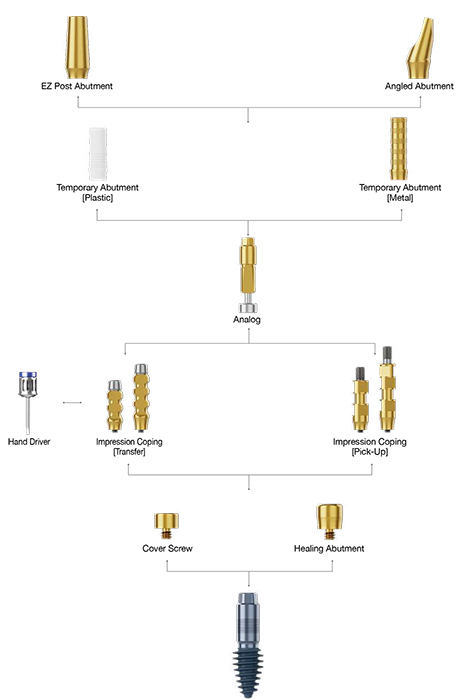

should be prepared to allow a one or two phase surgical approach according to the situation.

To avoid the inconvenience of modeling titanium membrane in the clinic, i-Gen has 12 pre-formed sizes in varying shapes.